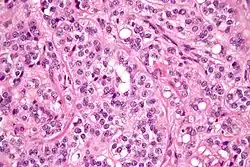

| Micrograph of a Sertoli cell tumour. H&E stain. | |

A Sertoli cell tumour, also Sertoli cell tumor (US spelling), is a sex cord–gonadal stromal tumour of Sertoli cells. They can occur in the testis or ovary. They are very rare and generally peak between the ages of 35 and 50. They are typically well-differentiated and may be misdiagnosed as seminomas as they often appear very similar.[1]

Microscopy and immunohistochemistry are the only way to give a definitive diagnosis, especially when there is a suspected seminoma.[3]